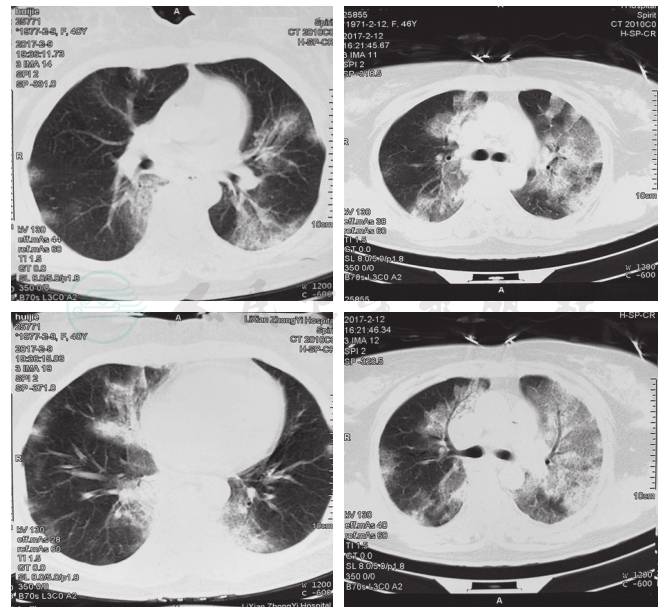

临床诊断考虑为社区获得性肺炎,病毒可能性大,同时应兼顾继发细菌感染的可能。治疗上给予奥司他韦75mg 2次/日,甲泼尼龙80mg 1次/日,亚胺培南西司他丁(泰能)、莫西沙星预防继发细菌感染,同时给予大剂量丙种球蛋白冲击治疗。入院初期,患者脉氧饱和度不易维持,明显喘憋,给予持续高流量呼吸湿化治疗仪治疗(氧浓度45%)。为尽早明确致病原,入院后立即留取咽拭子标本和支气管肺泡盥洗液送检,结果提示:肺泡盥洗液中性粒细胞24%,细胞总数0.68×106,甲型H1N1流感病毒核酸检测阳性(北京市疾病预防控制中心),确诊为甲型H1N1流感,继续原治疗方案治疗。治疗期间患者体温未升高,咳嗽、咳痰、呼吸困难等症状逐渐减轻,入院3天后复查咽拭子和支气管肺泡盥洗液:甲型H1N1流感病毒核酸检测均为阴性;5天后停用奥司他韦,激素逐渐减量,停用抗生素。后复查血气分析提示氧分压较前明显改善,2017年2月21日复查胸部CT示双肺片状、磨玻璃和实变影较入院前明显吸收(图3)。患者自述无明显不适,顺利出院。嘱出院后继续口服甲泼尼松龙片40mg 1次/日两周,加强营养,注意休息,定期复查胸部CT,呼吸科门诊随诊。

图3 胸部CT(2017-2-21):双肺片状、磨玻璃和实变影较前明显吸收